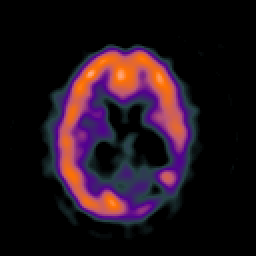

SPECT TC Study #8 -- Slice #33

[Home][Help][Clinical][Tour 1][Tour 2][Tour 3] Slice 33